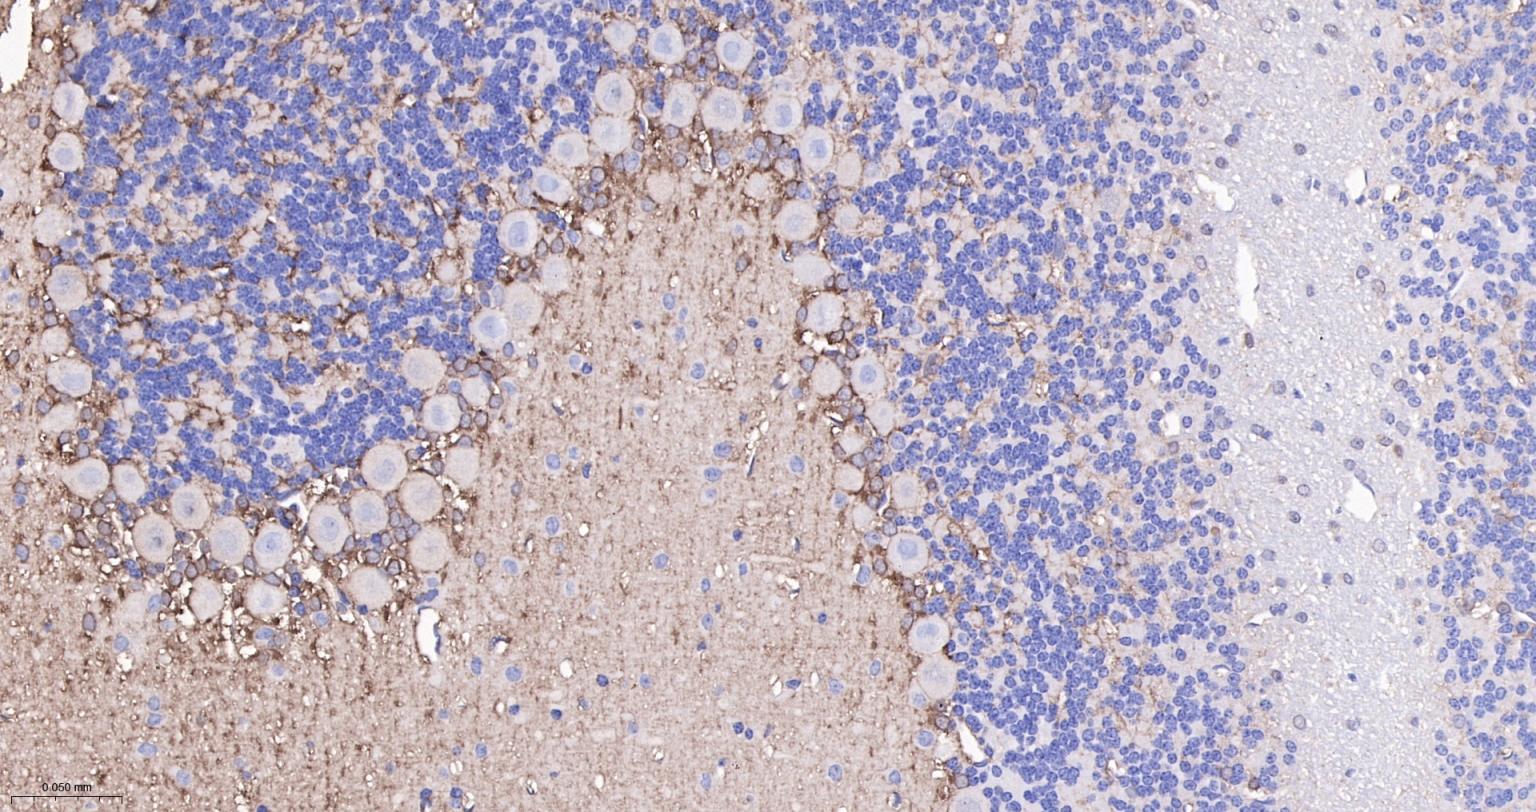

| IHC-P | Human, Mouse, Rat | 1:100-500 | |

| IHC-F | Human, Mouse, Rat | 1:100-500 | |